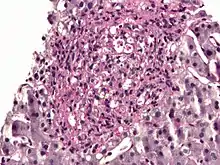

PAS diastase showing Histoplasma in a liver biopsy.

Periodic acid–Schiff–diastase (PAS-D, PAS diastase) stain is a periodic acid–Schiff (PAS) stain used in combination with diastase, an enzyme that breaks down glycogen. PAS-D is a stain often used by pathologists as an ancillary study in making a histologic diagnosis on paraffin-embedded tissue specimens. PAS stain typically gives a magenta color in the presence of glycogen. When PAS and diastase are used together, a light pink color replaces the deep magenta. Differences in the intensities of the two stains (PAS and PAS-D) can be attributed to different glycogen concentrations and can be used to semiquantify glycogen in samples. In practice, the tissue is deparaffinized, the diastase incubates, and then the PAS stain is applied.